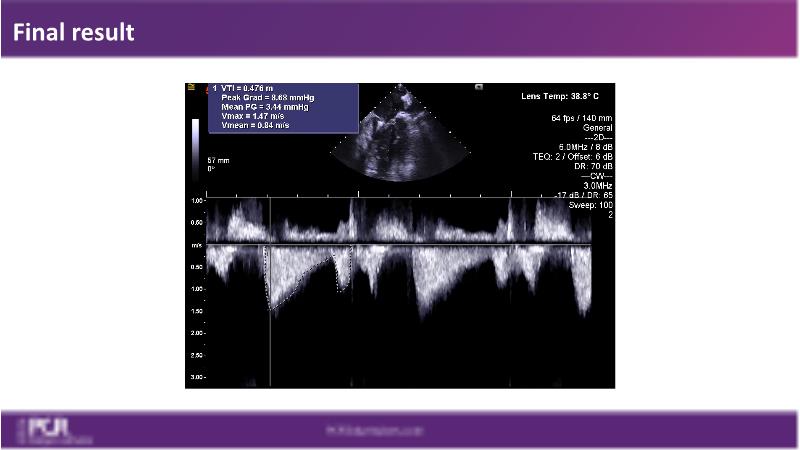

Watch this session to get an overview of a new TEER device, follow the step-by-step procedure related to initial experiences with this device for a Japanese patient with degenerative mitral regurgitation, learn about the latest data from RCT and registries, and follow discussions of challenging TEER cases!